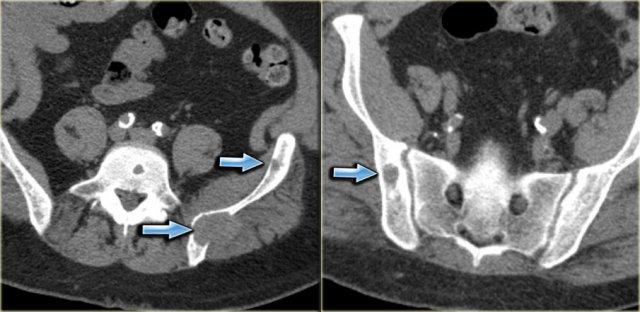

Hyperparathyroidism

U nâu có thể xuất hiện ở bất kỳ xương nào và biểu hiện dưới dạng tổn thương tiêu xương với bờ rõ nét.

Có thể thấy các vách ngăn và gờ xương.

Chẩn đoán phân biệt: Nang xương phình mạch (ABC), di căn và u tế bào khổng lồ (GCT) tùy thuộc vào vị trí và độ tuổi.

Bên trái là bệnh nhân đã được cắt thận do ung thư biểu mô tế bào thận và đang chạy thận nhân tạo.

Nhiều tổn thương tiêu xương bờ rõ được phát hiện trên phim chụp CT theo dõi.

Chẩn đoán phân biệt bao gồm di căn xương và u nâu trong cường cận giáp.

Sinh thiết xác nhận u nâu.

Discriminators:

- Must have other signs of HPT.